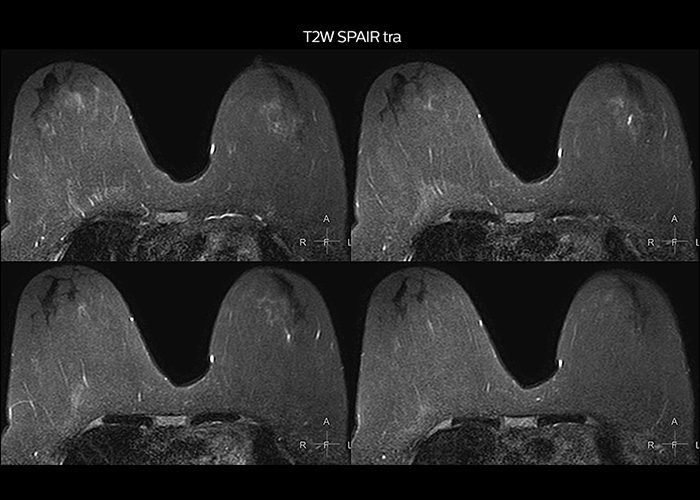

“To avoid coil changes we plan examinations of similar anatomies back to back, such as head and spine. Multiva helps us here a lot because coils don’t need to be changed frequently. Moreover, thanks to parallel imaging technology and 16-channel HeadSpineTorso and 8-channel MSK coils we are able to achieve excellent image quality. In this way Multiva helped us to increase both image quality and productivity.”

“Most important, Multiva satisfies our clinical imaging needs very well,” says Mr. Tuna. “Many features of Multiva have become similar to the Ingenia system. Even in more complex imaging such as abdominal and cardiac, the image quality and performance of Multiva is better than we expected. General surgeons and physicians from our hospital’s internal medicine department prefer to refer to us because of this.”